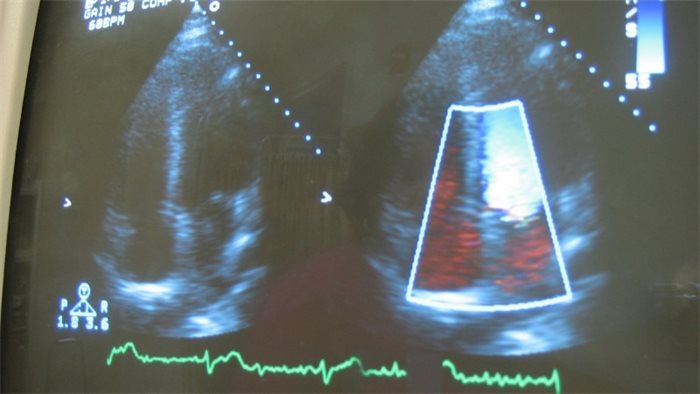

Heart scan - credit Sam Felder CC2.0

The number of people dying early from heart and circulatory disease has risen in Scotland for the first time in 50 years, the British Heart Foundation (BHF) has reported.

Heart and circulatory diseases cause around thirty per cent of all deaths in Scotland, but after decades of improvements, in 2017 more than 2,000 people under 65 died from heart disease or stroke, an eight per cent increase since 2014.